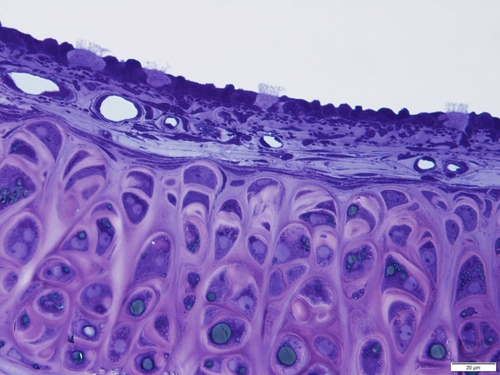

気 管(ラット) Trachea ( rat )

厚さ1 µm エポン樹脂準超薄切片のトルイジンブルー染色光学顕微鏡画像

Light microscopic image of 1 µm-semithin epoxy resin section with toluidin-blue staining

気管には粒子状物質の排除に関与する線毛細胞 ciliated cell が観察されます。